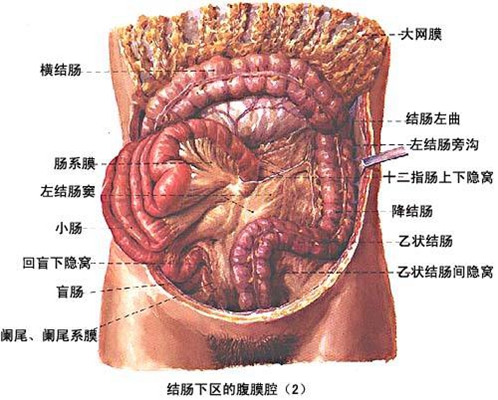

盲腸的位置 (50)

盲腸的位置 (6)

盲腸的位置 (7)

盲腸的位置 (8)

盲腸的位置 (9)

盲腸的位置 (46)

盲腸的位置 (47)

盲腸的位置 (48)

盲腸的位置 (49)

盲腸的位置 (5)

盲腸的位置 (42)

盲腸的位置 (43)

盲腸的位置 (44)

盲腸的位置 (45)

盲腸的位置 (41)

盲腸的位置 (40)

盲腸的位置 (30)

盲腸的位置 (31)

盲腸的位置 (32)

盲腸的位置 (33)